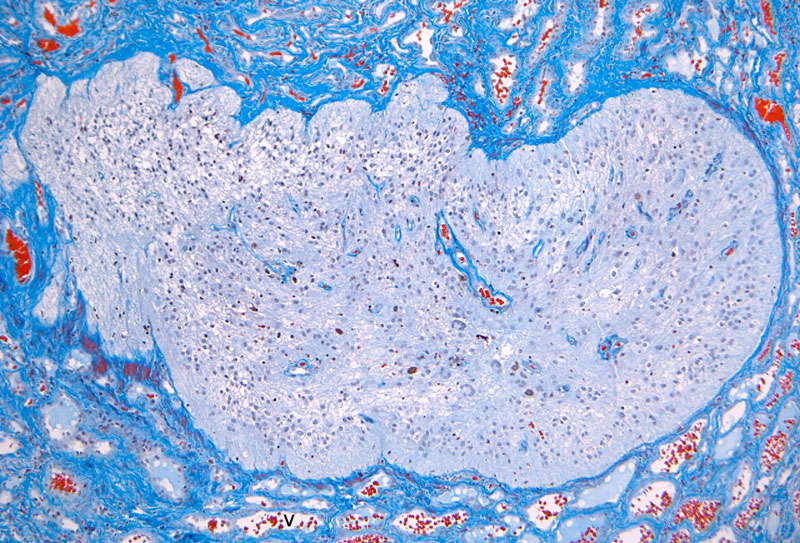

Hematoxylin & eosin

Area 4: Large neurons like the one being illustrated here are present in different part of the specimen. Can you find them? These neurons are large enough to compare with those in the anterior horn cells. This morphologic similarities, however, are not enough proof that these are anterior horn cells.